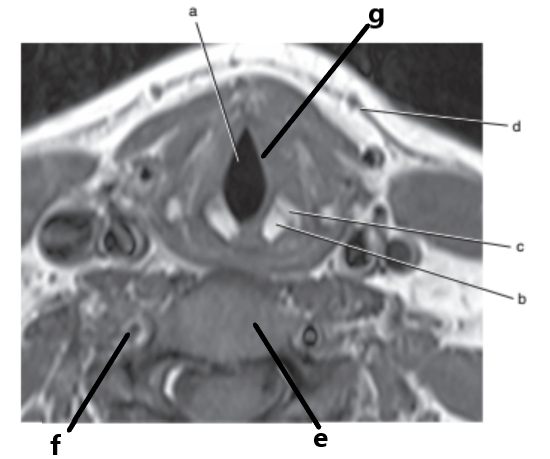

Sternocleidomastoid muscle

Vocal cords

Trachea

Spinal cord

What imaging plane is this ?

transverse